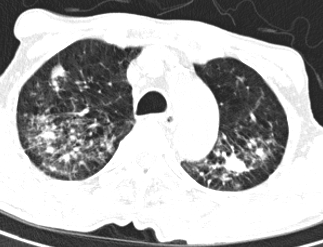

Tương tự, trường hợp người bệnh T.X.K (49 tuổi) ở Việt Trì, Phú Thọ dù không có dấu hiệu bất thường về sức khỏe nhưng khi kiểm tra cũng phát hiện người bệnh bị lao phổi, kết quả chụp X-Quang cho thấy tổn thương cả hai đỉnh phổi (hang lao, thâm nhiễm và xơ hoá).

| Hình ảnh X-Quang phổi của người bệnh T.X.K cho thấy hang lao đỉnh phổi trái và thâm nhiễm, xơ hoá hai đỉnh phổi - Ảnh BVCC |